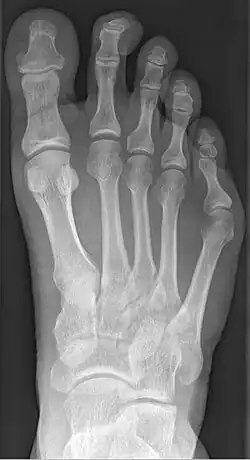

| Radiograph showing a tailor's bunion | |

Tailor's bunion is easily diagnosed because the protrusion is visually apparent. X-rays may be ordered to help the surgeon find out the severity of the deformity.